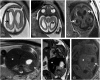

Human cytomegalovirus (CMV) is an ubiquitous pathogen, with a high worldwide seroprevalence. When acquired in the prenatal period, congenital CMV (cCMV) is a major cause of neurodevelopmental sequelae and hearing loss. cCMV remains an underdiagnosed condition, with no systematic screening implemented in pregnancy or in the postnatal period. Therefore, imaging takes a prominent role in prenatal diagnosis of cCMV. With the prospect of new viable therapies, accurate and timely diagnosis becomes paramount, as well as identification of fetuses at risk for neurodevelopmental sequelae. Fetal magnetic resonance imaging (MRI) provides a complementary method to ultrasound (US) in fetal brain and body imaging. Anterior temporal lobe lesions are the most specific finding, and MRI is superior to US in their detection. Other findings such as ventriculomegaly, cortical malformations and calcifications, as well as hepatosplenomegaly, liver signal changes and abnormal effusions are unspecific. However, when seen in combination these should raise the suspicion of fetal infection, highlighting the need for a full fetal assessment. Still, some fetuses deemed normal on prenatal imaging are symptomatic at birth or develop delayed cCMV-associated symptoms, leaving room for improvement of diagnostic tools. Advanced MR sequences may help in this field and in determining prognosis, but further studies are needed.